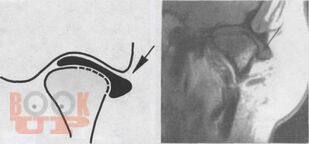

В данном учебном пособии рассмотрены актуальные вопросы современной гнатологии. Большое внимание уделено особенностям анатомии и кинематическим характеристикам височно-нижнечелюстного сустава и жевательных мышц. В доступной форме изложены основные и дополнительные методы обследования пациентов на гнатологическом приеме. Подробно рассмотрены гнатологические аспекты оценки функциональной окклюзии в норме и при патологии жевательного аппарата. Последовательно представлены ключевые моменты по вопросам устройства и настройки аппаратов, имитирующих движения нижней челюсти (артикуляторов). С современных позиций изложены основные клинические варианты окклюзионной терапии.